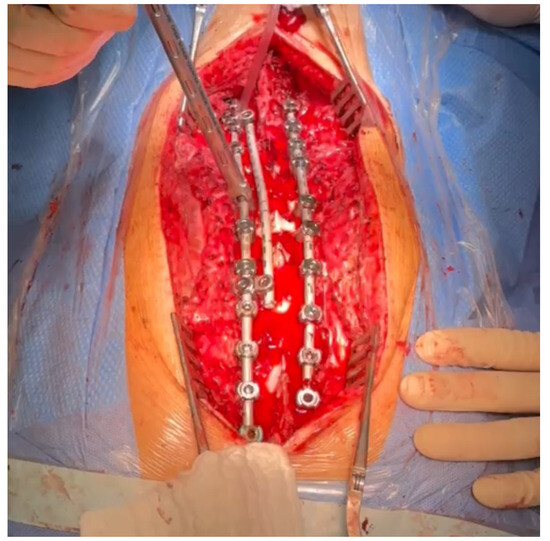

The patient required surgical treatment. We considered several alternatives for the management of this severe case: continued observation (controversial for congenital cases), continued bracing/casting (controversial for congenital cases), in situ fusion and spinal cord decompression, an anterior/posterior approach, decompression, spinal fusion, lateral retropleural/retroperitoneal corpectomy, and posterior spinal fusion. We analyzed the indications, contraindications, and risks of potential surgical treatment using various techniques. Due to the extensive experience of our center in the comprehensive treatment of severe and neglected congenital spinal deformities, a one-stage treatment using a posterior approach was planned—a posterior-only vertebral column resection via a lateral extracavitary approach at T11 and anterior spinal fusion for the T10–T12 vertebrae with the addition of an anterior structural titanium cage in the VCR site and posterior spinal fusion from the T4 to the L3 levels. The rationale for the procedure was the failure of conservative management; a progressive increase in curve magnitudes over time; progressive mechanical back pain upon sitting, standing, and lying; sagittal imbalance; an inability to maintain a balanced, upright posture for prolonged periods; and, finally, a high risk of neurological deficits and paraplegia. However, like any surgical procedure, the one we planned was burdened with potential complications and the risk of failure. The risks of the procedure include neurovascular injury/spinal fluid leak, neurological deficits, implant prominence, post-surgical junctional kyphosis, adding-on, pull-out of screws/rod fractures/pseudarthrosis, hardware malposition, infections, and revision surgery. The benefits of the procedure are as follows: reconstitution of thoracolumbar junction alignment, improved coronal and sagittal alignment of the spine, stabilization of spine deformity progression, curve correction, global sagittal balance, balancing of shoulder asymmetry, decreased back pain, potential reduction in the risk of paraplegia, and improvement in health-related quality of life [11]. We performed a one-stage posterior surgery, positioning the patient in a prone position on an open Jackson table using neuromonitoring (SSEP, MEP), C-arm, and surgical loupes [12,13]. The most important technical steps for the surgical procedure were: pedicle screw placement using a free-hand technique under neuromonitoring control (6.5 and 60.0 multiaxial screws from T5 to L3; transverse process hook placed bilaterally at T4 to prevent pullout and PJK), peri-apical Ponte’s osteotomies (at T9–L1) as shown in Figure 4, temporary rod placement, P-VCR at T11 using a titanium mesh cage for anterior column reconstruction as presented in Figure 5, deformity correction via compression and in situ techniques, and temporary rods being bent and replaced with contoured rods to achieve adequate sagittal and coronal balance [14] as shown in Figure 6.

Figure 5. Temporary rod placed, P-VCR at T11 performing power burr, preparing for placement of a titanium mesh cage for anterior column reconstruction.